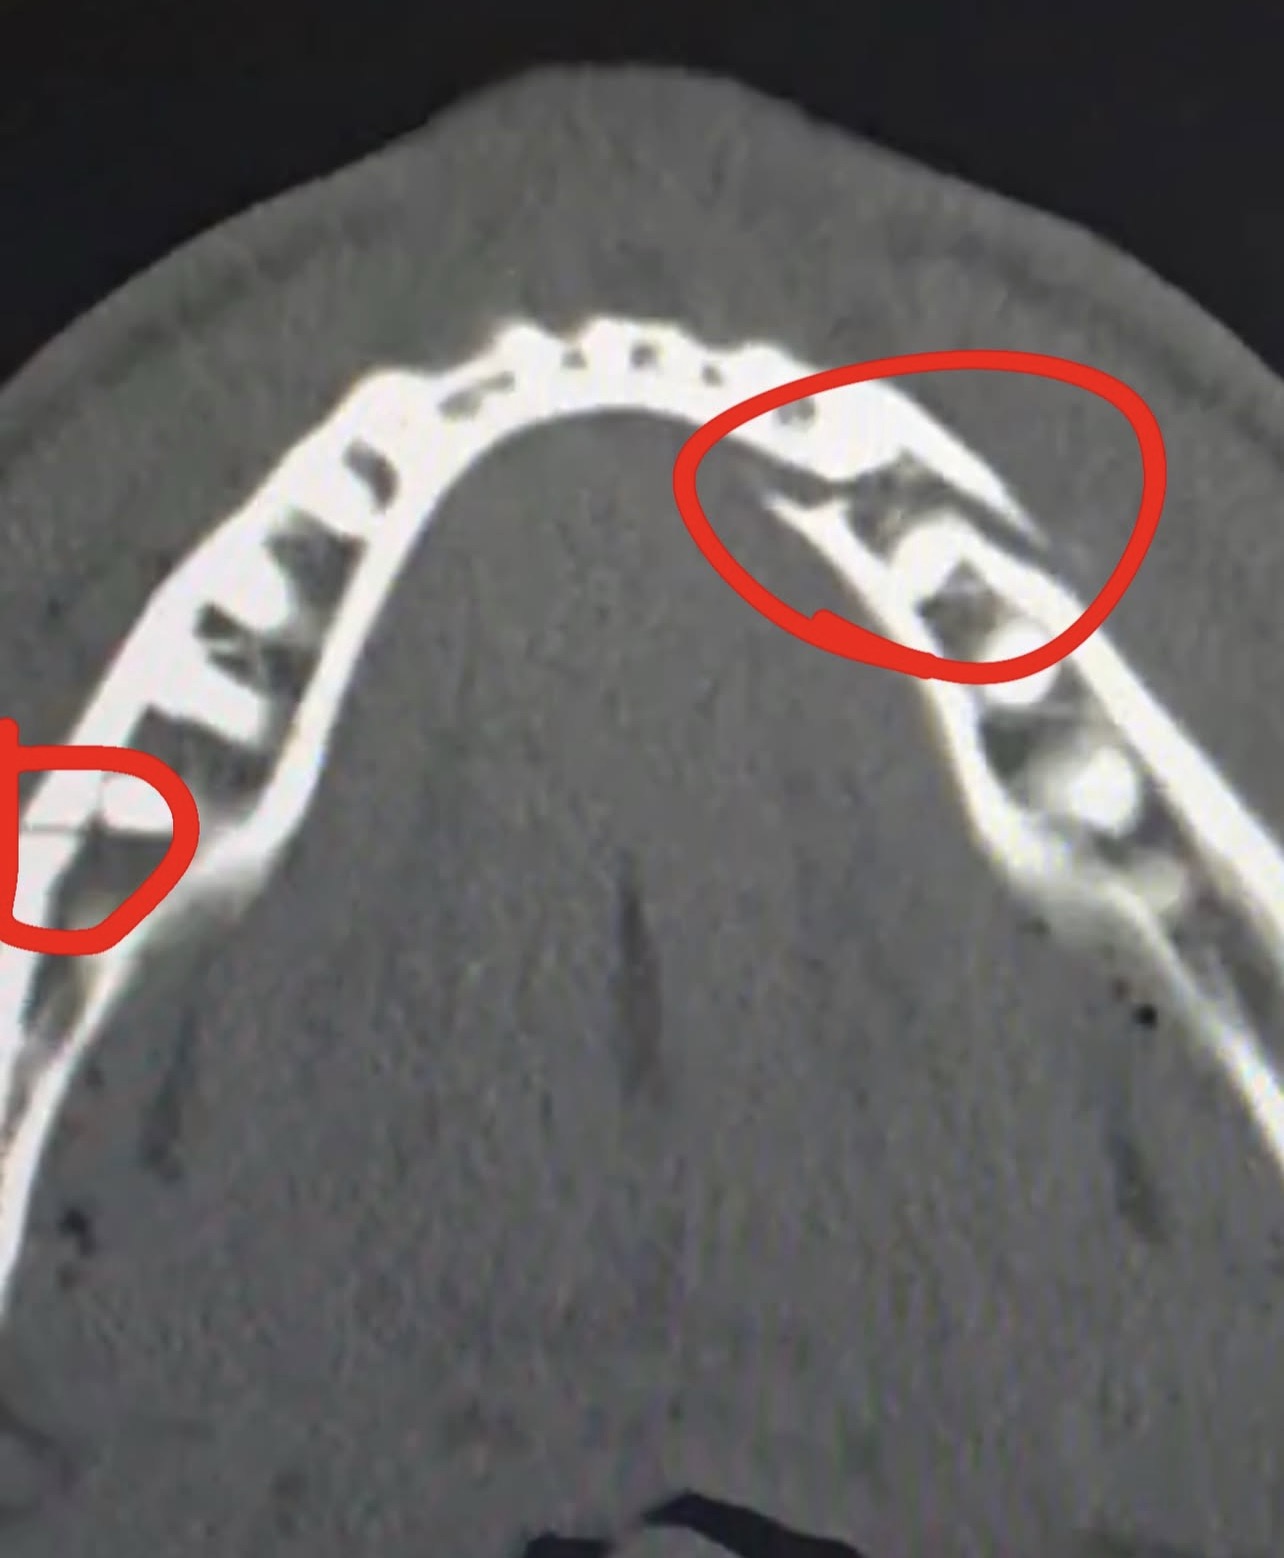

«Перелом щелепи у двох місцях. Дайте мені Канело через 10 днів», — написав Джейк.